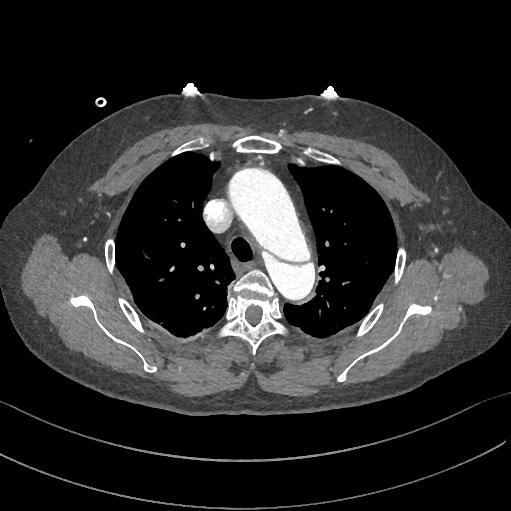

下图的胸部CT平扫,有什么大问题?

图1

火眼金睛的小伙伴可能发现了,主动脉有问题,动脉破裂了?

图2

然而,先冷静!这个阴影是半月形的略高密度阴影,是片状的,是不均匀的,这个是伪影!增强扫描,主动脉很正常!

图3